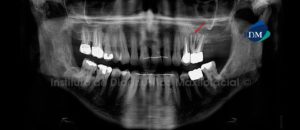

Paciente femenino de 55 años de edad que es referida por presentar dolor en la pieza 26. La radiografía panorámica nos muestra un trazo de